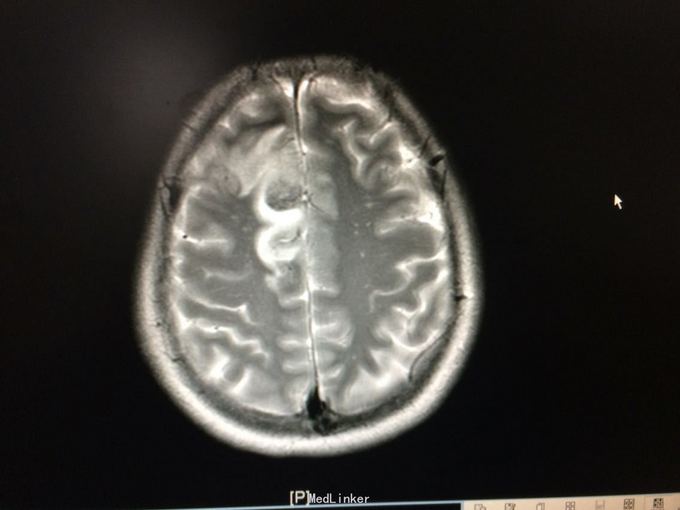

主诉:记忆力减退3月,左侧肢体乏力3天 病史:患者51岁女性,3月前无明显诱因出现记忆力减退,伴头痛,3天前出现站立不稳,左侧肢体乏力,步行困难,当地CT提示右侧额叶低密度灶,

查体:左侧上肢肌力4级,右侧5级,轻瘫试验左侧阳性 辅助检查:右侧额叶、胼胝体膝部病变伴出血,增强扫描明显强化。考虑胶质瘤

诊断:右侧额叶多发脑软化灶 处理:全麻下行右侧额叶占位病变切除术,术后病理提示:符合脑软化,未见明显肿瘤因素等